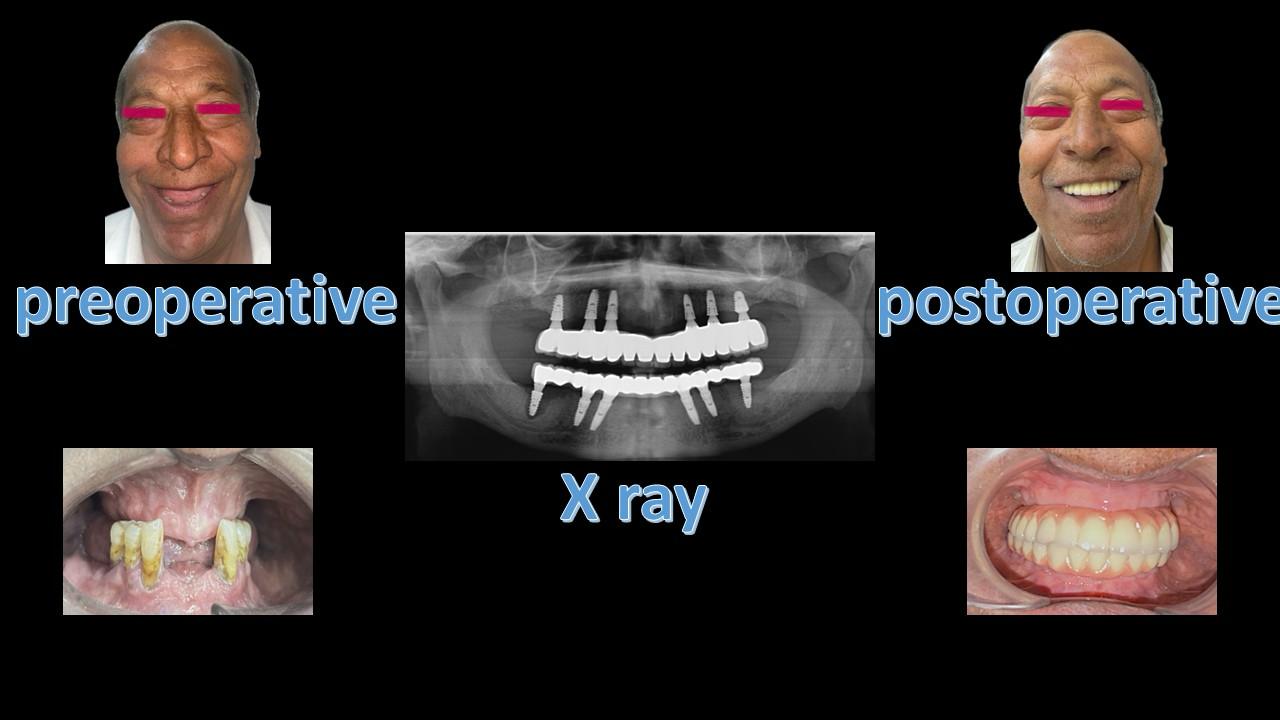

At Smile Dental Care Centre, we invite you to discover our exceptional dental care services in Delhi. We proudly hold the title of the best dental clinic in East of Kailash, Delhi and Faridabad, with a dedicated team of skilled dentists committed to preserving your oral health and enhancing your smile.

With two convenient locations in East of Kailash and Faridabad, we are even more accessible to serve your needs. Our state-of-the-art facility offers a wide range of services, including routine check-ups and advanced cosmetic and restorative procedures. Prioritizing your comfort, we employ the latest technology and gentle techniques for a pain-free experience.

At Smile Dental Care Centre, your health is our main concern. Our best dentist in Faridabad and Delhi provide friendly and personalized care to fit your needs and give you a happy, healthy smile. We’re also at the forefront of dental technology, using the latest advancements to ensure the best possible care for you. Get in touch today to set up your appointment!